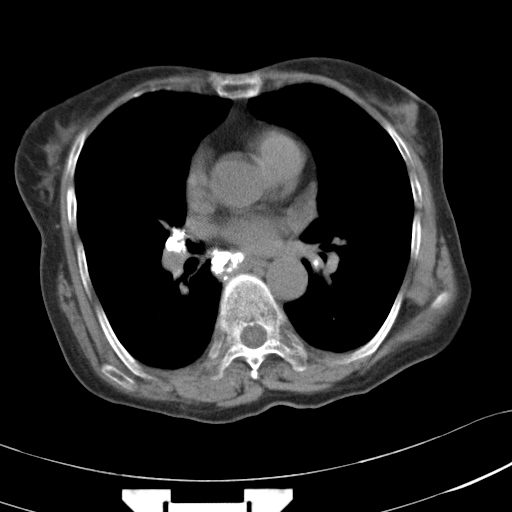

以下是引用hhcckk在2007-3-2 14:51:00的发言:[br]考虑结核球可能性大,依据[br]1病灶在下叶背段,结核的好发部位[br]2病灶内有大量的钙化,纵隔内有大量的淋巴结钙化[br]3重要的是半年前与现在相比无变化,假如是肿瘤的话不会这么‘善良’[br]4病灶周围卫星灶不明显,病灶有毛刺,胸膜凹陷,肿瘤不能完全排除,有条件的话最好做个活检

以下是引用liuyue在2007-3-2 17:15:00的发言:[br]1位置:右上叶后段[br]2性质:大分叶、粗长毛刺、条状斑片状钙化、纵隔多发淋巴结钙化,无强化,故考虑:肺结核灶(陈旧)